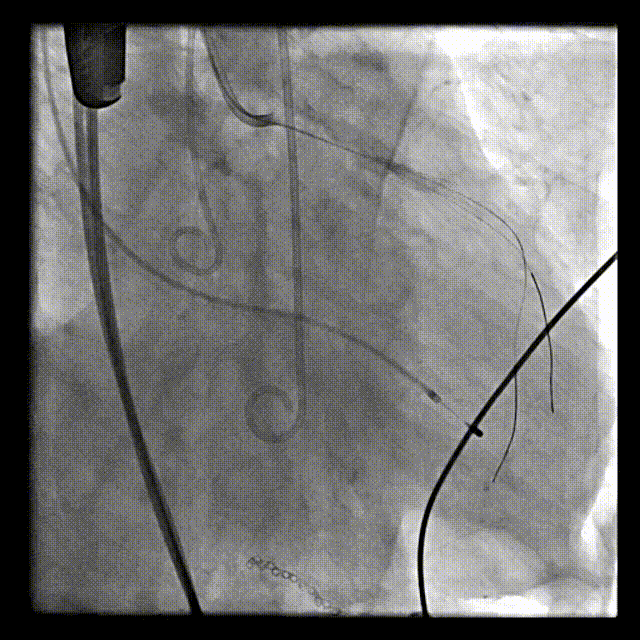

在医务处协调下,心胸外科、麻醉科、重症医学科、体外循环组做详尽预案的充分准备下,张俊杰教授成功完成了这一例高难度的TAVR+PCI手术,在全麻和ECMO湿备的保护下,术中首先采用双支架技术成功处理LAD/D1复杂分叉病变,随后成功植入VitaFlow 30瓣膜,术后植入IABP辅助患者的心功能的恢复,并转ICU进一步治疗。

瓣膜稳定释放

释放后造影:瓣膜位置良好,无瓣周漏